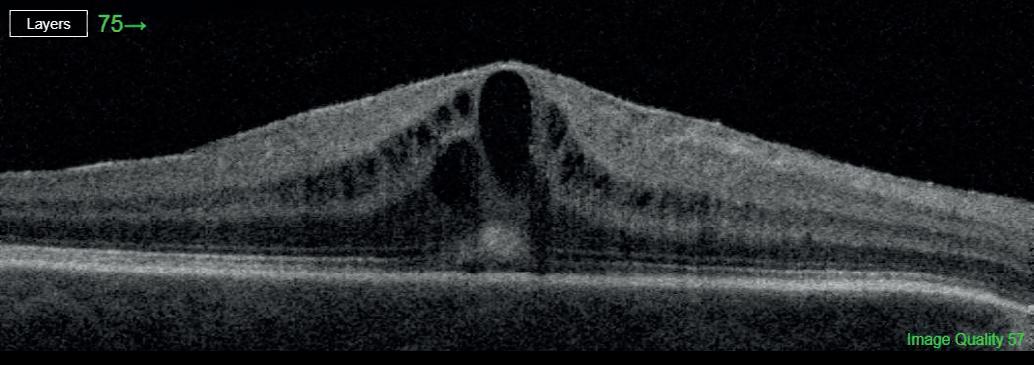

Most astronauts experience changes to the structures of their eyes and brains while in space flight, including swelling at the back of the eye called optic disc oedema (ODE).

The size of effects and time of onset of ODE varies widely between individuals. While changes tend to be reversed when crew members return to Earth, there are concerns that extended missions, such as those being proposed to the moon and Mars, could increase the risk of permanent vision problems.

US-based researchers analysed data on 31 astronauts who spent six to 12 months on the International Space Station. They found that 23 of the astronauts developed signs of ODE. Average total retinal thickness increased from a pre-flight average of 392.0μm to 430.2μm after around 150 days in space.

It has previously been suggested that those with a small or non-existent optic cup, an area at the centre of the optic disc, are more at risk of developing ODE during spaceflight (Stenger et al, 2019).

In the new study, published in JAMA Ophthalmology, the researchers found that astronauts with small, shallow and narrow optic cups pre-flight experienced larger increases in retinal thickness while in space. No other pre-flight ocular measures were associated with ODE.

Only six women took part in the study, so it is limited in its applicability to female astronauts. It was also not possible for in-flight measurements to be collected after the same number of days, and the length of time since participants had taken part in previous space missions was not considered.

The findings, nonetheless, support the idea that astronauts with smaller optic cups may benefit from increased monitoring and use of countermeasures. bit.ly/3igZr70